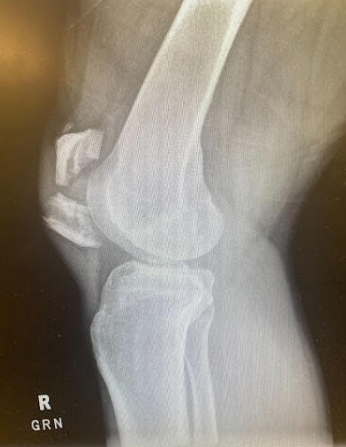

A 21-year-old female presents to the emergency room after falling from dancing on a table and injuring her right ankle. She is in severe pain and unable to bear weight comfortably with swelling and tenderness along the lateral malleolus. X-rays are taken and shown above.